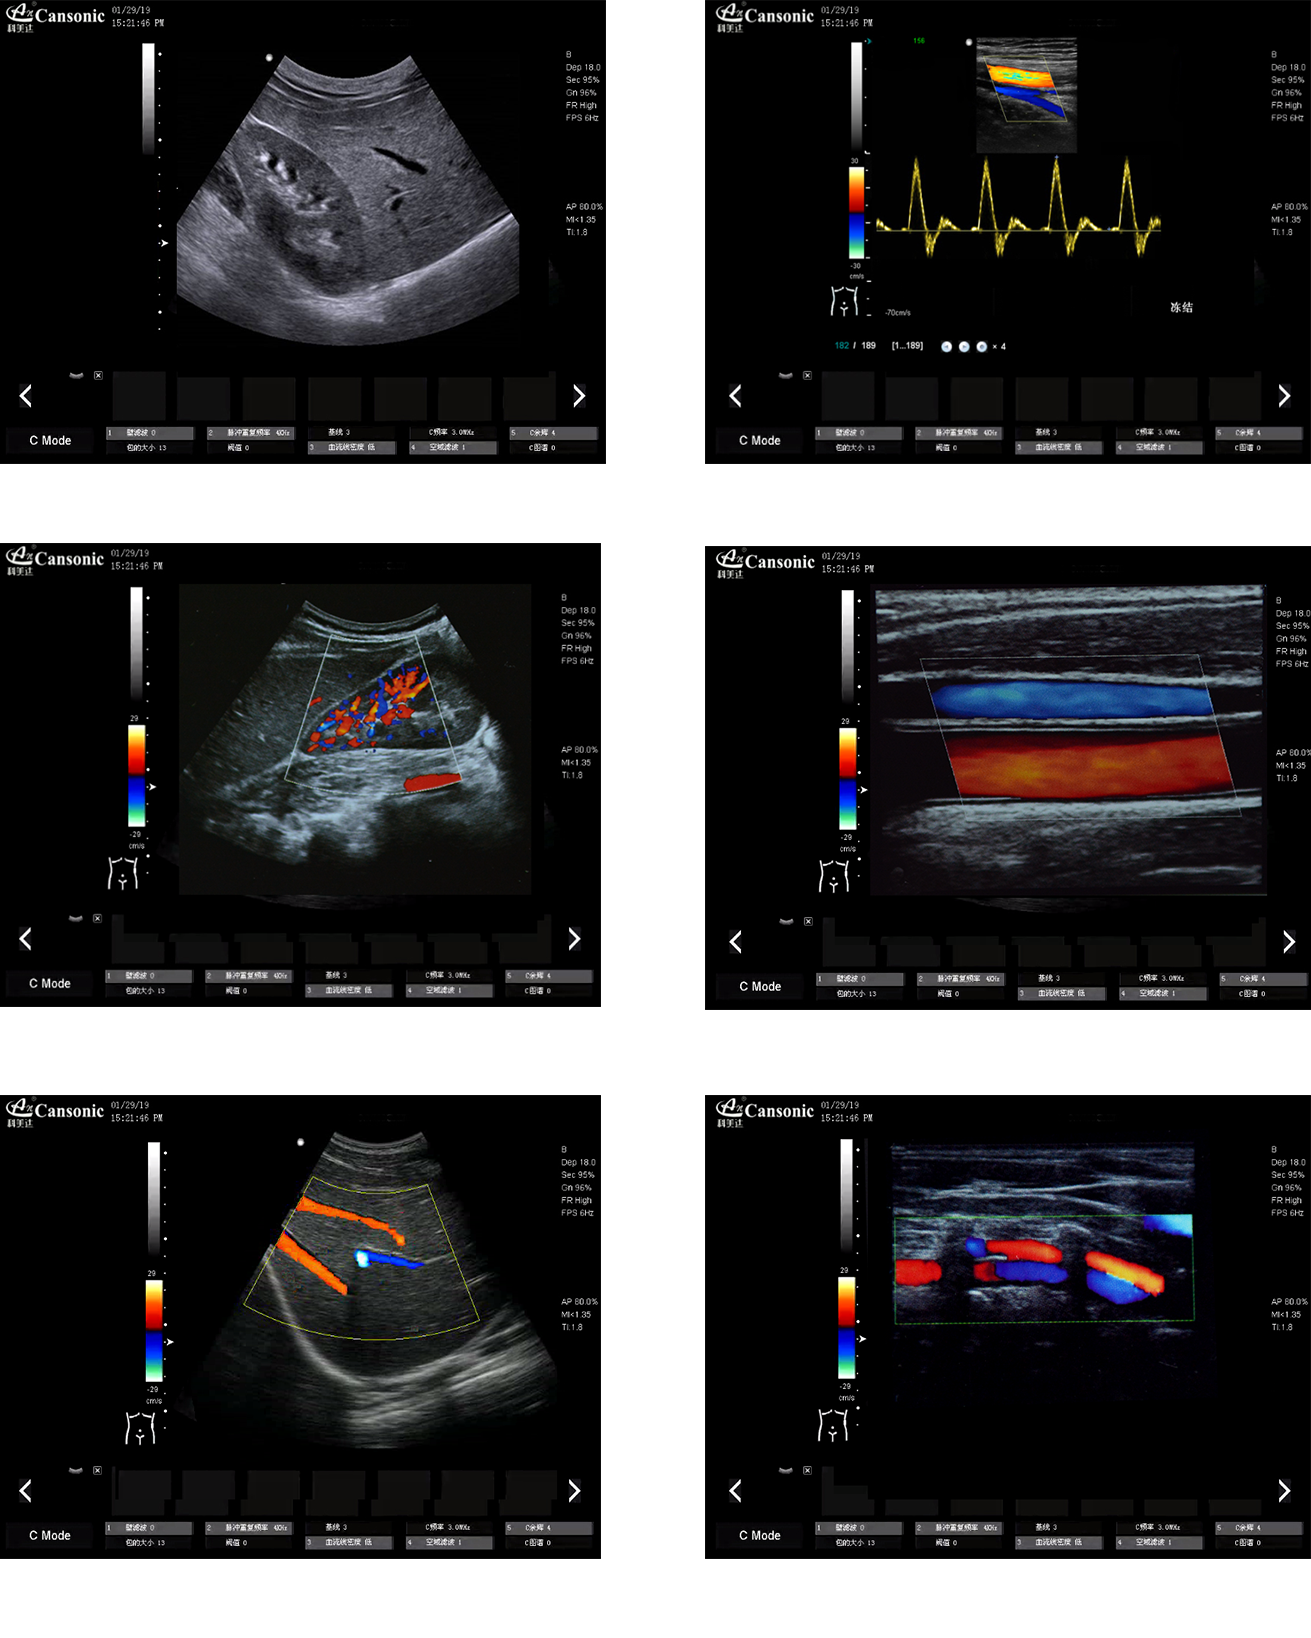

科美達(dá)K10圖像實(shí)例

1、薈萃前沿成像技術(shù),以優(yōu)異的圖像質(zhì)量滿足全面的臨床應(yīng)用

3、脈沖反相諧波功能,提高軸向分辨率,減少圖像偽影,提高診斷率

4、選擇手動(dòng)或自動(dòng)包絡(luò)頻譜,提高效率,一鍵顯示各種血流動(dòng)力學(xué)數(shù)據(jù)

5、精準(zhǔn)濾波技術(shù),降低噪聲干擾,提升血流靈敏度。